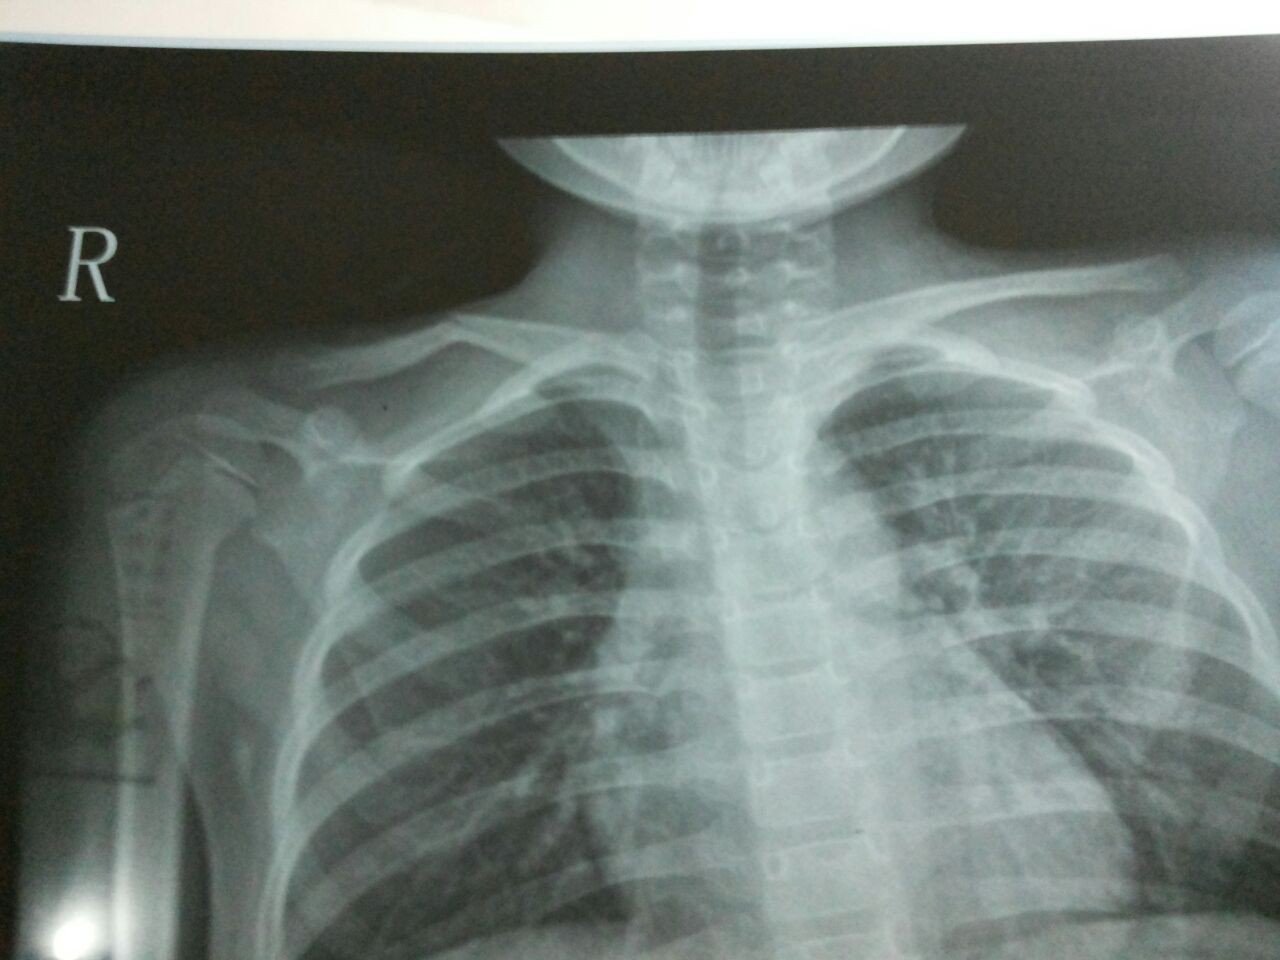

2013年8月18号22点多我家小孩5周岁她从床上摔下来马上去医院检查拍照锁骨断裂拍片如下

医生说5岁小孩建议保守治疗想问一下有没有更好的建议意见。小孩子平时(饮食。睡觉及护理等方面)应该注意些什么。孩子还小会不会给小孩留下后遗症

此部位很容易长的,不用手术,稍微绷带固定包扎一下就行。 背个钢丝架恐怕孩子会很不适应的。 这种骨折一般不留下后遗症。

对位还是可以,对线很差,不过小孩的骨头可塑性很高,而且锁骨功能不多,生长愈合就可以。如果拍影响外观,可以手法复位后固定。